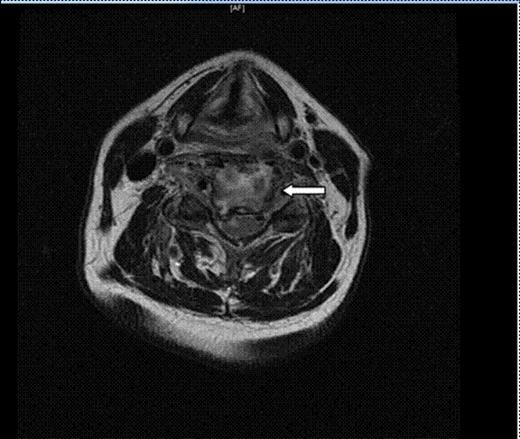

Axial T2 FSE cervical image. There is enhancement of the C4 and C5 vertebral bodies consistent with osteomyelitis